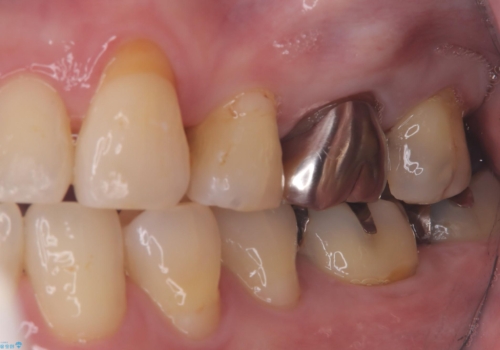

- 主訴:フロスを通したら、詰め物が取れた。適合の良いものを入れたい。

保険適用のメタルインレーが脱離しており、適合重視・咬合力が強いことからゴールドインレーでのやり替えとなりました。

フロスを通しインレーが脱離したことから、インレーと歯質との境に段差(適合不良)があった可能性があり、適合の良さや咬合力による補綴物の破折リスクを考慮し、ゴールドインレーでのやり替えとなりました。